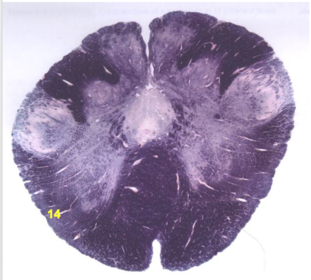

| Medullary pyramids | |

| Hypoglossal nucleus | |

| Hypoglossal nerve | |

| Dorsal motor nucleus of X | |

| Nucleus ambiguus | |

| Solitary tract | |

| Solitary nucleus | |

| ALS | |

| Medial lemniscus | |

| Medial longitudinal fasciculus | |

| Anterior spinocerebellar tract | |

| CN IX | |

| Inferior cerebellar peduncle | |

| Inferior olivary complex | |

| Dorsal cochlear nucleus | |

| Inferior vestibular nucleus | |

| Medial vestibular nucleus | |

| Spinal nucleus of V | |

| Spinal tract of V | |